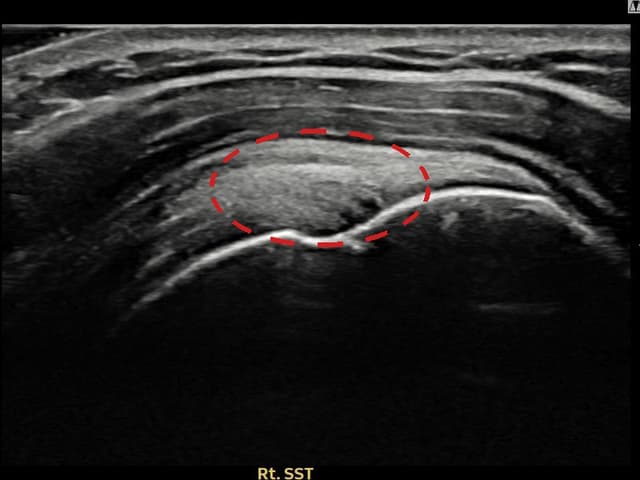

右侧 冈上肌腱 石灰化肌腱炎

10mm × 7mm